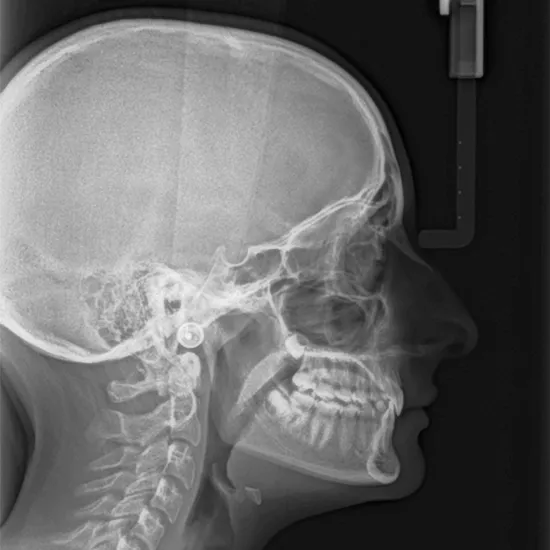

The right or left lateral view of the skull demonstrates pathology such as skull fractures. The “lateral skull base” is one unique area of the skull base, situated at the side of the skull. This part of the skull base comprises structures called the temporal bone, infra-temporal fossa, clivus, and middle and posterior fossa.

This view is useful in assessing:

• Skull fracture

• Clivus

• Sella turcica

• Clinoid

• Nasal Bone

• Mandible fracture

• Internal auditory meatus

• Skull circumference

• Paget disease

• Neoplastic change

• Ethmoid sinus

• Orbits

• Structure seen in the dental region

• Mastoid sinus